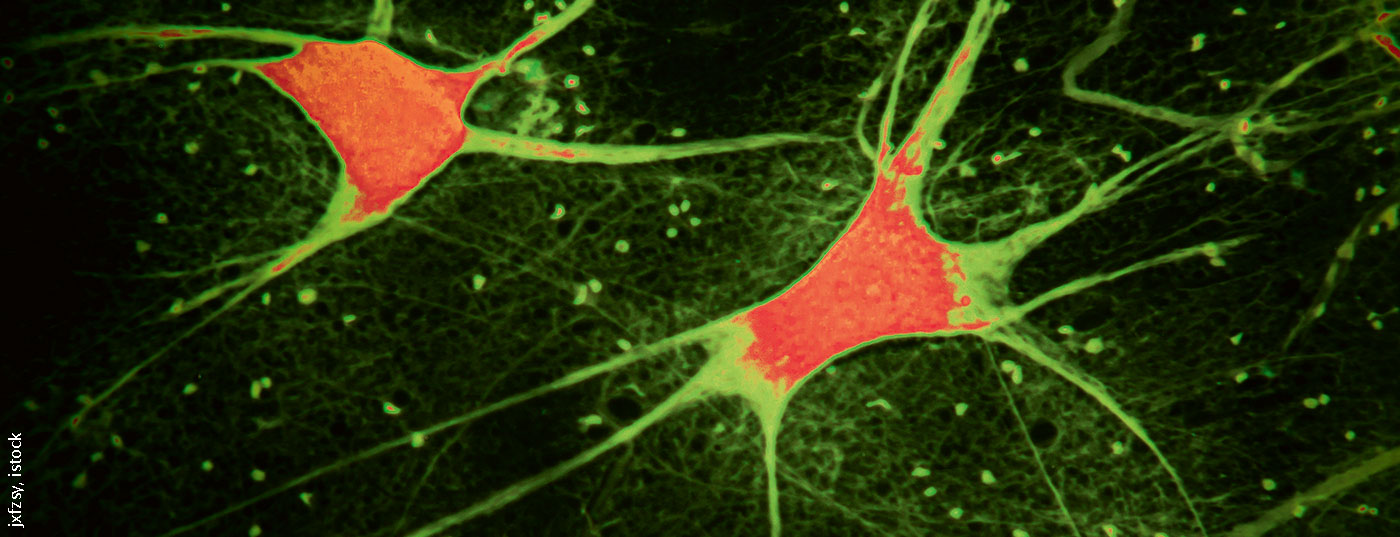

Die Behandlung erwachsener Patienten mit 5q-assoziierter spinaler Muskelatrophie Typ II und III mit Nusinersen wird in der Schweiz per 1. Juli 2020 vergütet. Die Kostenübernahme erfolgt über die Spezialistätenliste (SL) der obligatorischen Krankenpflegeversicherung. Dies ist für Betroffene eine grosse Erleichterung, bisher war ein ärztlicher Antrag auf Vergütung im Einzelfall die einzige Möglichkeit für eine Erstattung.